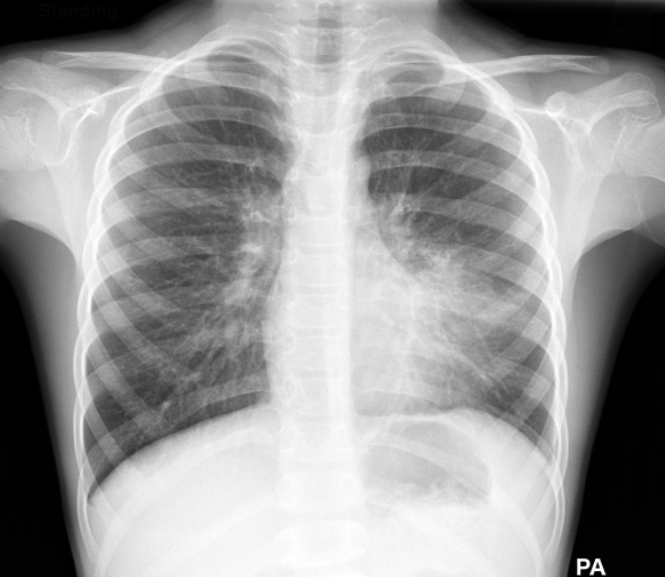

🦠폐렴, 소아에서 왜 더 주의해야 할까요?

소아에서 흔하게 발생하는 폐렴, 단순 감기로 생각하고 넘기기엔 위험할 수 있습니다. 아이의 면역력과 폐 기능은 아직 미숙하기 때문에 폐렴에 쉽게 노출되고, 빠르게 진행될 수 있죠. 이번 글에서는 소아 폐렴의 증상부터 진단, 치료, 예방까지 보호자분들이 꼭 알아야 할 정보를 정리해드립니다.1. 🤒폐렴이란? 감기와 다른 점은?폐렴은 폐에 염증이 생긴 상태로, 바이러스나 세균, 마이코플라즈마 같은 다양한 병원체가 원인입니다.감기는 상기도(코, 인후) 감염이지만, 폐렴은 **하기도(기관지, 폐포)**를 침범해 호흡곤란이나 흉부통증이 나타날 수 있습니다.구분감기폐렴발열미열고열(39도 이상)기침마른기침심한 기침, 가래호흡정상빠르고 힘든 호흡식욕조금 감소많이 감소전신 상태비교적 양호처지고 지쳐 보임 2. 🫁폐렴의..